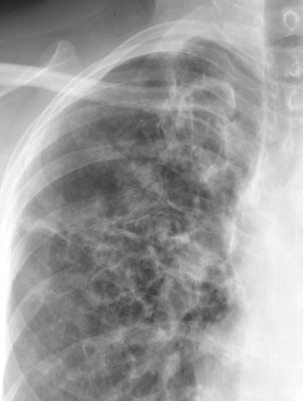

Gallery COPD ABPA cu

ABPA cu